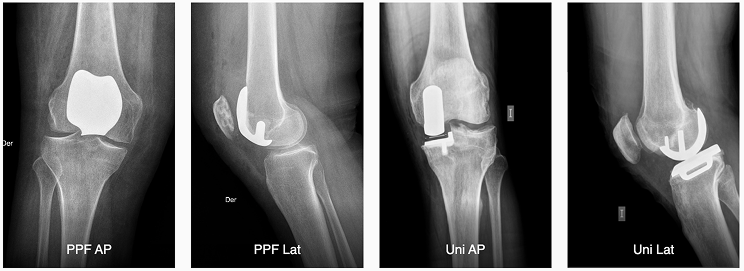

Como equipo, desde el 2020 también incorporamos la cirugía robótica de rodilla a nuestros servicios, a través del robot ROSA Knee, tecnología que asiste a los traumatólogos durante la operación y que permite devolver movilidad a la rodilla.